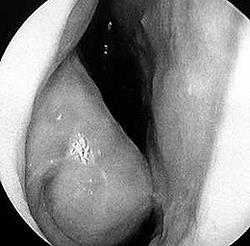

Местные изменения. Слизистая оболочка носа имеет синюшно-бледный цвет, в острой стадии заболевания она может быть темно-красной. Раковины носа отечны, в полости носа большое количество прозрачного секрета.

При осмотре можно обнаружить нарушение строения лица, аномалии прикуса, постоянно открытый рот, темные круги под глазами и поперечную складку над кончиком носа. Часто наблюдается отек конъюнктивы с зудом, слезотечением и гиперемией. С помощью носового зеркала выявляют отек, рыхлость и синюшность слизистой оболочки, прозрачную слизь; дыхательные пути могут быть сужены отечными носовыми раковинами. Густые гнойные выделения из носа свидетельствуют об инфекции. Аллергическому риниту нередко сопутствуют синусит, средний серозный отит, экзема или бронхиальная астма.